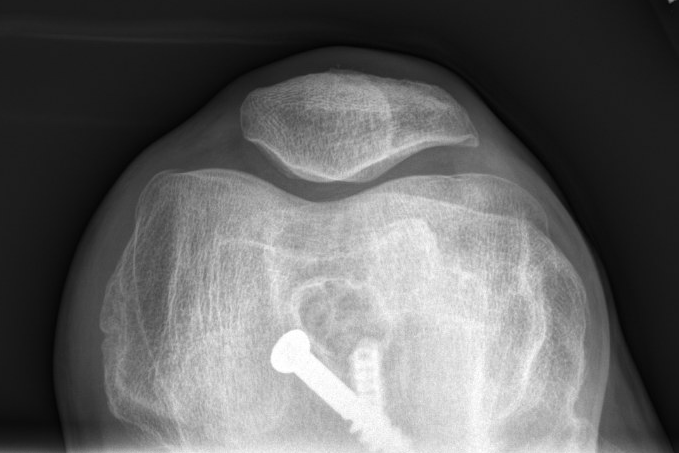

Hello #orthotwitter

55 y/o F, 3 mo post-op, pain with WB since 1 mo.

PMHx unremarkable, non-smoker. Pain constant, ↑ with ambulation, ↓ with rest, ↑ with flexion >90°

Neutrophils 72

ESR 45

CRP 10

PCT normal

Thoughts?

@kneedoclond @EdinburghKnee @aberizzi @drsebheaven